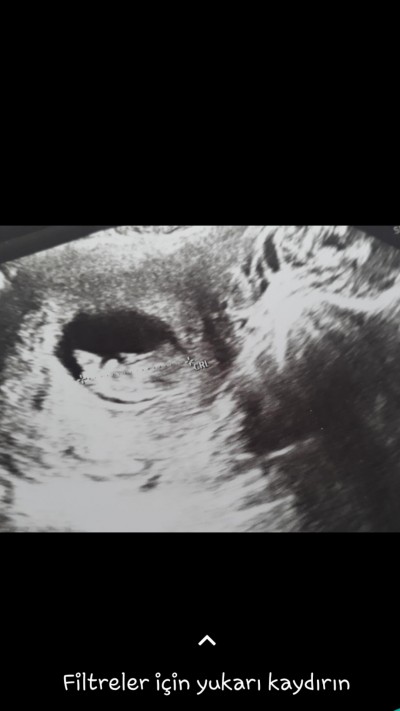

Sizce cinsiyetimiz nedir canlar benim içime erkek doğuyor ama bilemiyorum

Gebelik haftası 10+3

bende 9+5 günlük 10 haftada gidicem ins doltor o kadarrrrr uzmandir ki bi tahminde bulunur o bile beni mutlu eder :D seninki erkek gibi acmis bacaklarini kizlar genelde kapatir gosteemez derler tabi bi tahmin dogrusunu allah bilir hayirli saglikli evlat olsun insallah

Nubu gorunmuyor kafa yapisi erkek gibi ama skull teosrisi genelde yanilabiliyor